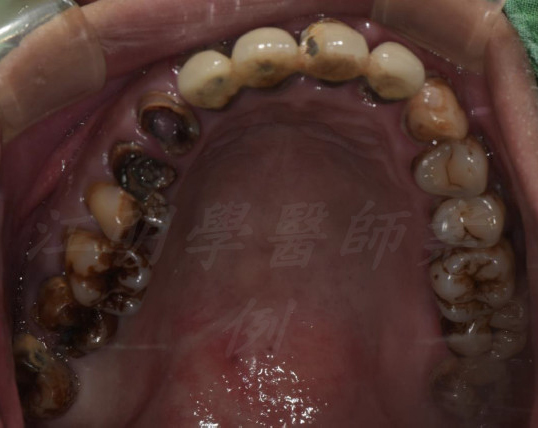

活動式假牙案例

牙齒狀況改善

治療前

治療後

這些照片展示了您的牙齒在術後得到顯著改善,排列更加整齊、美觀,並達到理想的咬合狀態。

也能增強口腔健康。